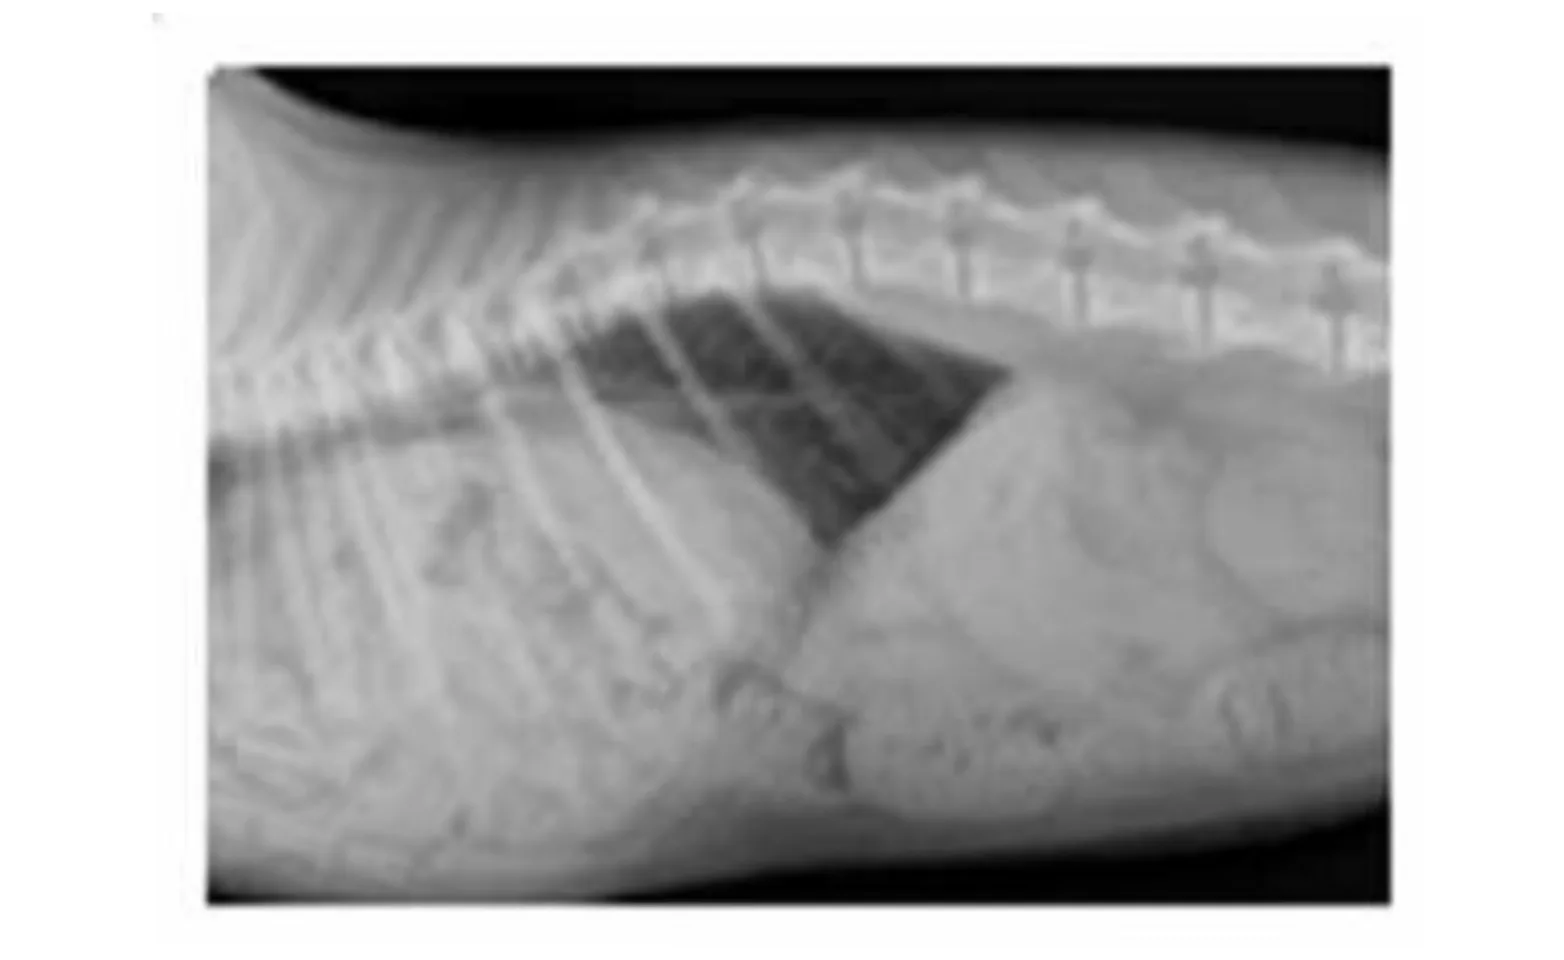

Many PPH are discovered as an incidental finding during routine thoracic and/or abdominal radiographs. Typical findings include enlargement of the cardiac silhouette and the presence of a soft tissue mass near the heart that is contiguous with the abdomen. If herniation of abdominal viscera has occurred, then bowel loops and/or liver can be seen adjacent to the heart on radiographs and sonogram. Because the thoracic cavity is not compromised, pneumothorax is not a typical finding and dyspnea is rarely observed.

Peritoneopercardial Hernias in Dogs and Cats Radiograph (Figure 1)